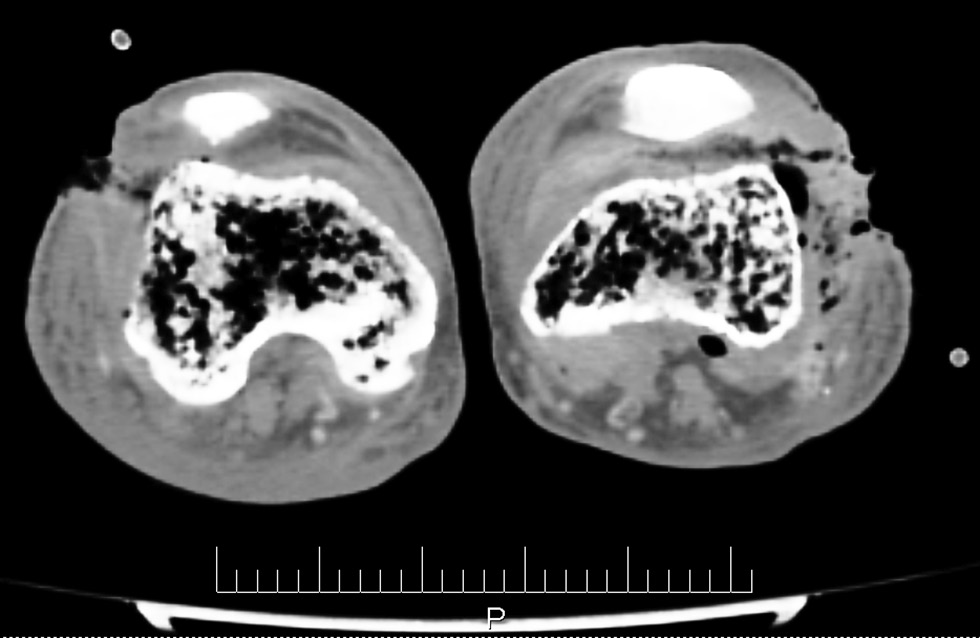

При компьютерной томографии коленных суставов у пациента выявлены деструктивные изменения в эпифизах костей и очаговые инфильтративные процессы в мягких тканях, прилежащих к суставам (рис. 2).

Рис. 2. Очагово-деструктивные и инфильтративные изменения костей и мягких тканей области коленных суставов пациента (по данным компьютерной томографии)